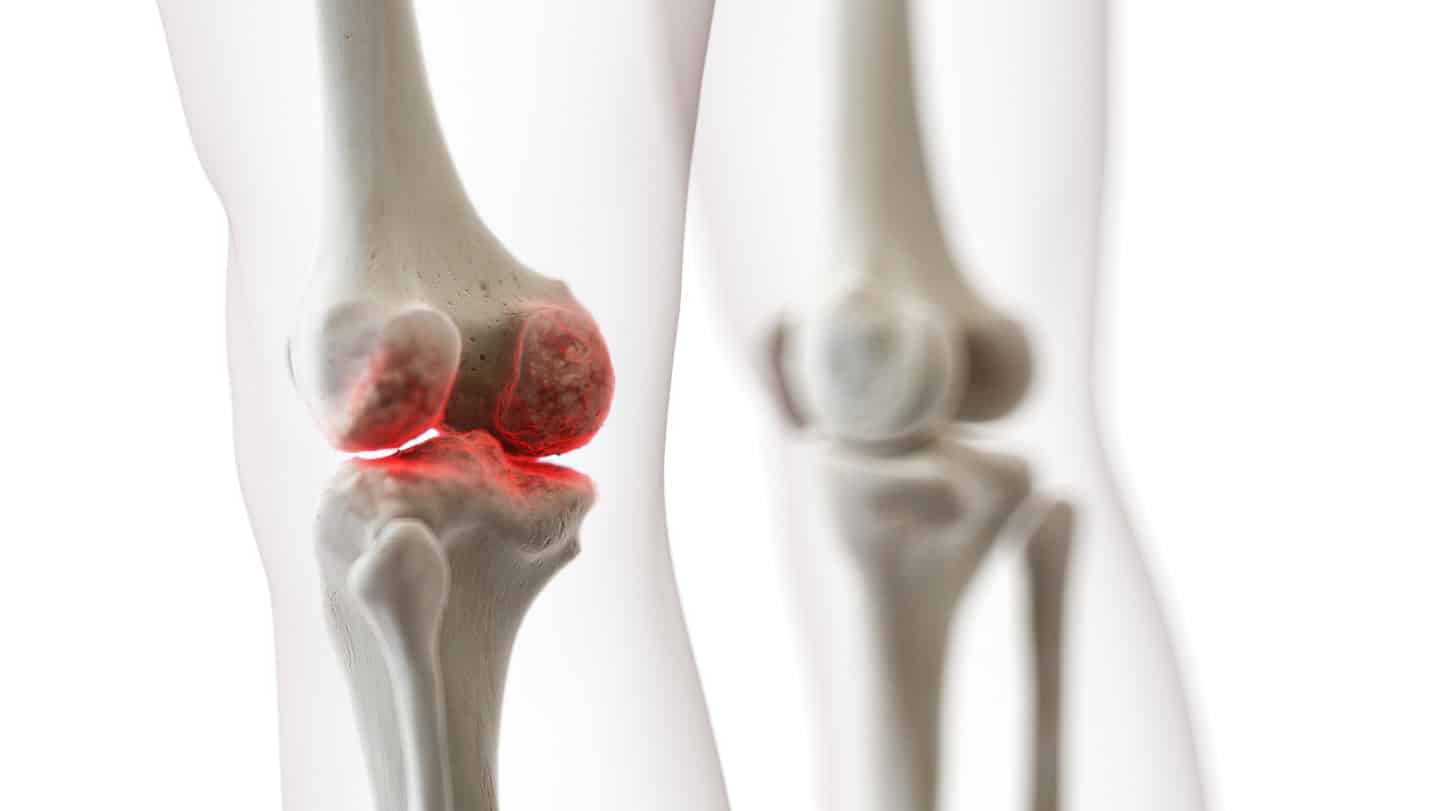

Complex Knee Deformities

Genu Valgum (Knock-kneed deformity) refers to an incorrect alignment around the knee where the knees bend inwards and “knock” against each other. If left untreated, this condition could lead to chronic pain and joint degeneration.

Genu Varum (Bow-legged deformity), conversely, refers to an incorrect alignment where the knees bend outwards, leaving a distinct space between the lower legs and knees.

Knee deformities may also happen as a result of two factors — significant trauma or impact to the knee, or changes developed from progressive arthritic conditions. Bones usually appear more prominent or push against the skin. This may cause significant pain, swelling and difficulty of movement.